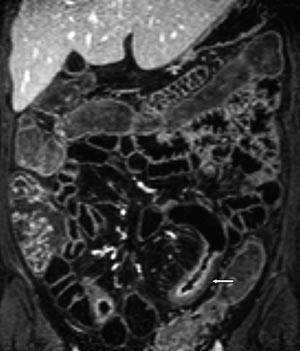

Vanlige MR-funn ved Crohns sykdom er fortykket tarmvegg (fig 5). Mer overflatiske forandringer i slimhinnen blir ikke optimalt fremstilt, men dypere ulcuser blir fremstilt, og dette er tegn på aktiv inflammasjon (fig 6). Både fibrose og aktiv inflammasjon i tarmveggen lader opp etter intravenøs kontrast. Det typiske for aktiv inflammasjon er en kraftig og lagdelt kontrastoppladning (fig 7), men den kan også være mer homogen.

Vår erfaring med MR av tynntarm skriver seg i hovedsak fra undersøkelser av pasienter med Crohns sykdom. Det finnes flere studier der man har sammenliknet MR av tynntarm med sonde og røntgen tynntarm med sonde med kliniske funn hos pasienter med denne sykdommen (1) – (6). Disse studiene viser at MR-undersøkelse er like bra som konvensjonell tynntarmsrøntgen for fremstilling av dype ulcuser og stenoser. Sensitiviteten var 100 % og spesifisiteten 75 % for fremstilling av dype ulcuser (3). Stenose ble påvist med en sensitivitet og en spesifisitet på 100 % (2, 3). Forandringer utenfor tarmen, som abscess og fistel, ble påvist i større grad med MR enn med konvensjonell røntgen og med en sensitivitet på henholdsvis 80 % og 70 % (4). I en studie fra 2004 ble MR-funn og røntgenfunn proksimalt for terminale ileum sammenliknet hos pasienter med kjent Crohns sykdom i colon eller terminale ileum (6). Det var samme funn i terminale ileum hos 23 av 25 pasienter med MR og med endoskopi. Ved hjelp av MR ble det påvist flere lesjoner proksimalt for terminale ileum enn det som ble påvist med konvensjonell røntgen. Overflatiske ulcuser er vanskelig å fremstille på MR pga. for lav bildeoppløsning. Disse fremstilles bedre med konvensjonell røntgen av tynntarm med sonde (3).

Tilsvarende sammenlikninger er også gjort for MR av tynntarm med oral kontrast og røntgen av tynntarm med enkeltkontrast hos pasienter med Crohns sykdom (7, 8). Funnene her viste også godt samsvar. I en studie sammenliknet man MR av tynntarm med sonde, røntgen tynntarm med sonde og MR av tynntarm med oral kontrast med kliniske funn hos 25 pasienter (9). Man fant at begge MR-metodene påviste veggforandringer, fistler og stenoser i like stor grad. Dette indikerer at sonde ikke er nødvendig ved kontroll av pasienter med allerede diagnostisert Crohns sykdom (14).